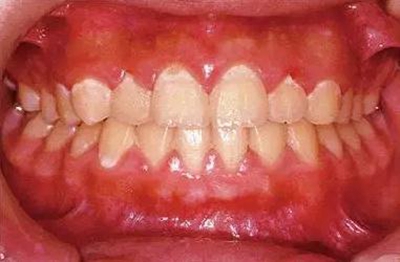

26歲男性牙齦炎的臨床圖像

26歲男性。開口呼吸?;旌嫌醒例l發(fā)紅、腫脹與纖維性肥厚。菌斑干燥牢牢黏住,刷牙難以刷掉。